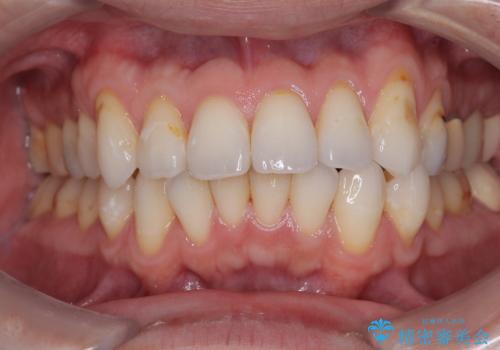

前歯をきれいにしたい オールセラミッククラウンにによる補綴